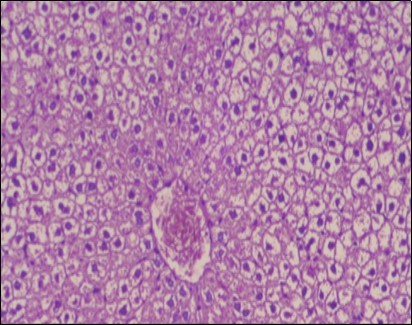

Effect of Ator, Fennel and Their Combination on the Liver of Obese Rats

The histological examination of the livers of control rats feeding standard diet showed normal architecture hepatocytes, blood sinusoid and central vein, figure 6. The rats which were fed on a (HFD), showed swollen hepatocytes with vacuolated cytoplasm filled with fatty infiltration, congested central vein and disappearance of blood sinusoids, figure 7. By comparison, the liver of rats that were treated by fennel after obesity and control mice observed nearly normal of the hepatocytes with eosinophilic cytoplasm, central vein and clear blood sinusoids and more bi-nucleated cells, figure 8. While examination of rats' liver that were treated by Ator and after the obesity appears, they showed mild fatty change in hepatocytes, few hepatocytes retain is eosinophilic cytoplasm and central vein figure 9. Liver of rats that were treated by fennel and Ator after obesity and control rats are showing nearly normal hepatocytes figure 10.

Figure 7.Photomicrograph of liver section of obese rat showing swollen hepatocytes with vacuolated cytoplasm filled with fatty infiltration, congested central vein and disappearance of blood sinusoids, (H&E) (40X).

Figure 8.Photomicrograph of liver section of treated rat with fennel herb showing nearly normal of the hepatocytes with eosinophilic cytoplasm, central vein (CV) and clear blood sinusoids and more bi-nucleated cells , (H&E) (40X).